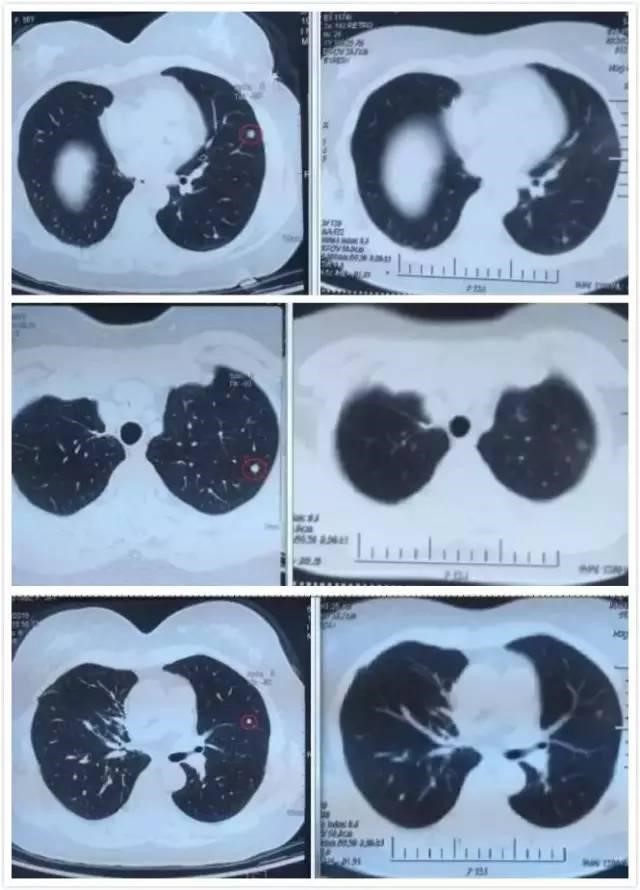

张女士治疗做完后回家,当时并不知效果如何,直到9月6日复查结果出来,显示肺上三个病灶消退,全家人都很开心,先生说,现在太太每天在家开心的逗孙子玩,自己感觉体力充沛了许多,每天可以走七八千步锻炼。院长穆向魁博士建议说,患者现在暂时不需要治疗了,回家休养,三个月后再进行一次巩固,增强免疫就好。

左图红色圈内是A45治疗前三个肺癌病灶,右图为治疗后病灶消失